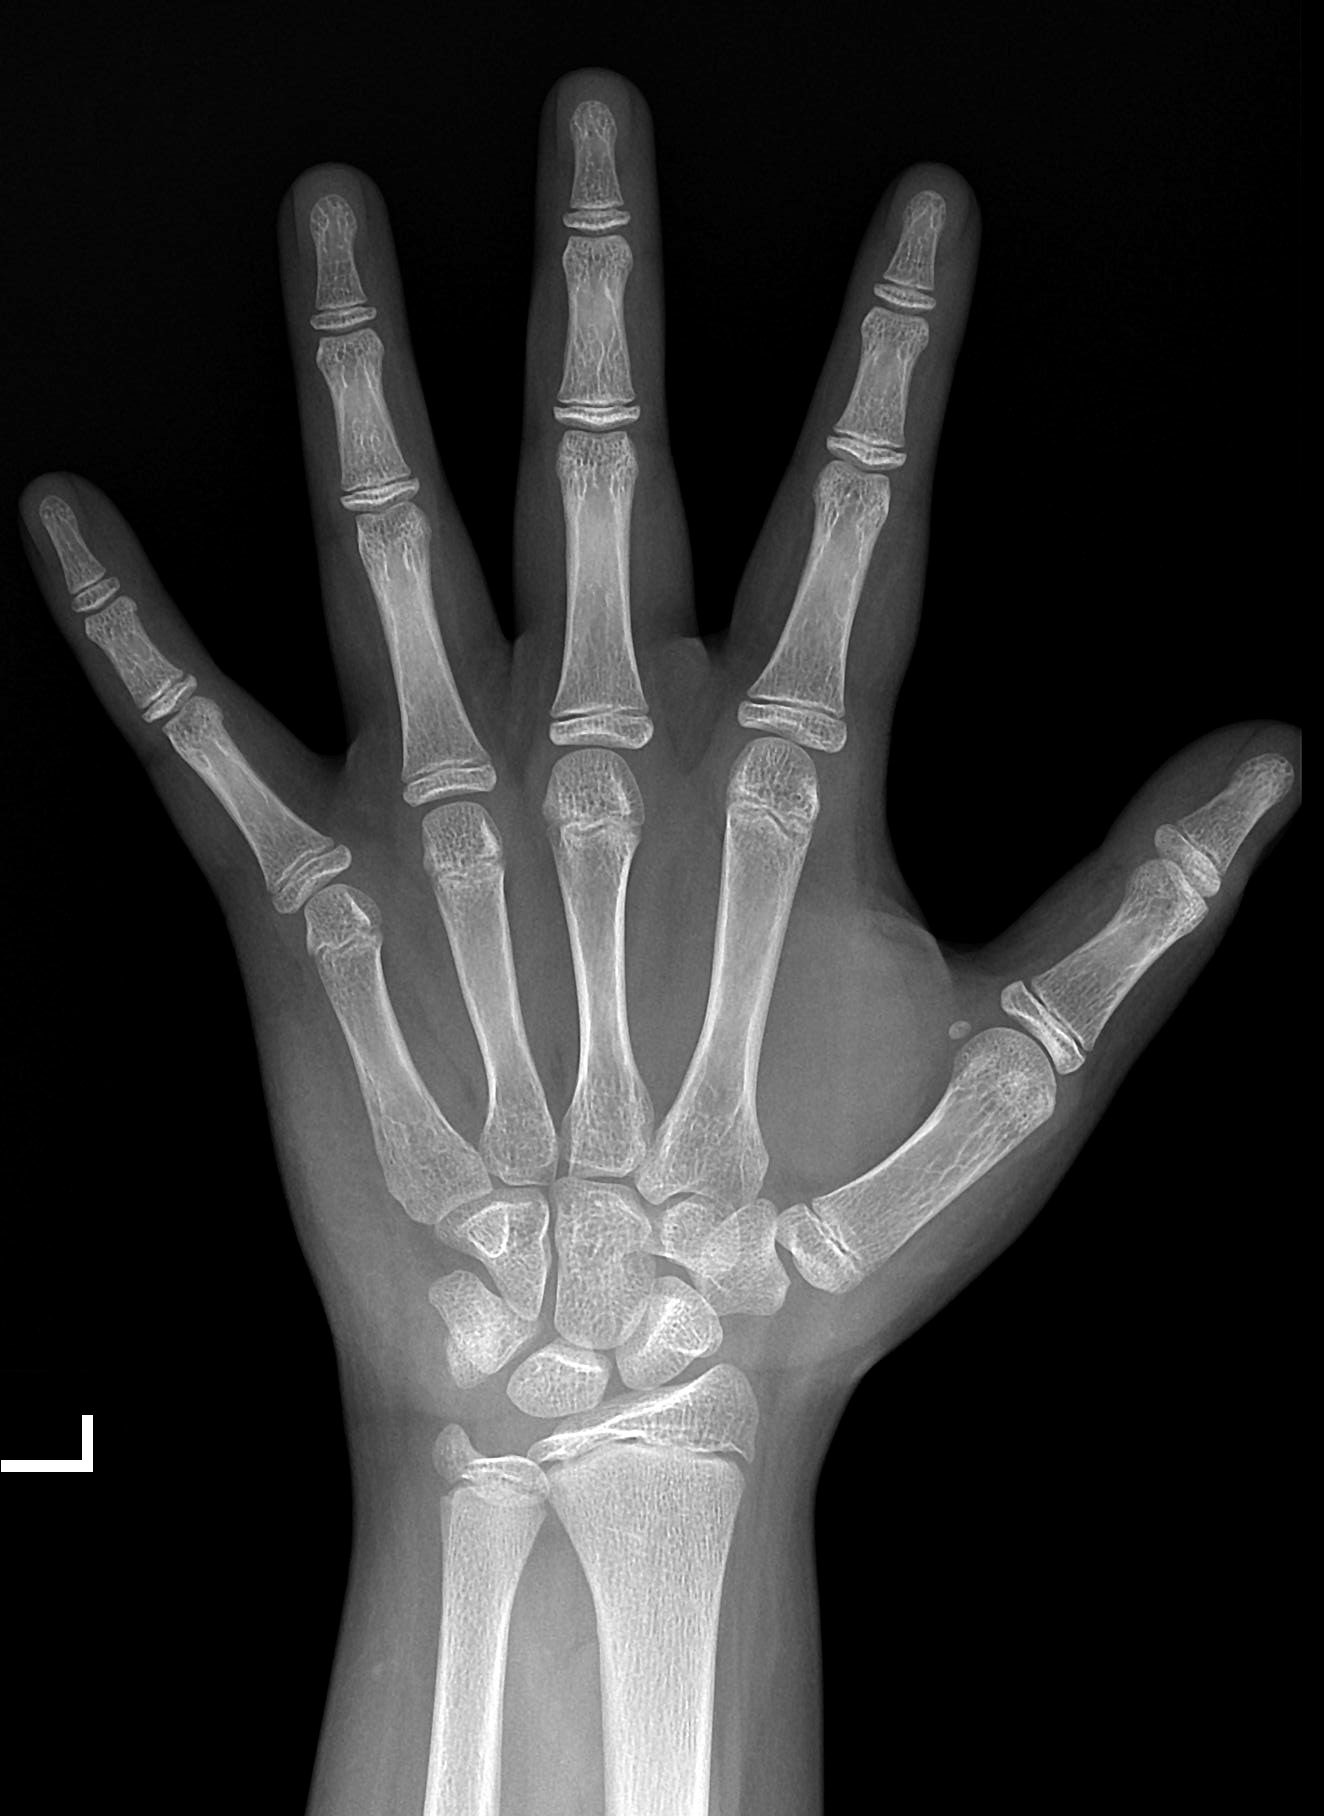

一、 骨龄整片

性别:男

RUS-CHN 骨龄:13.0岁

TW3-C RUS 骨龄:12.9岁

RUS-CHN是《中华-05》骨龄标准中的一种方法,在TW3基础上增加了骨发育等级分期,以中国当代儿童为样本制定,适用于当代中国儿童。

TW3-C RUS是《中华-05》骨龄标准中的一种方法,严格遵循了TW3方法的等级分期及SMS(等级得分),以中国当代儿童为样本重新绘制了骨龄百分位数曲线,适用于当代中国儿童。